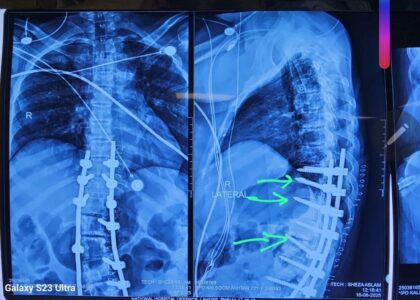

Successful Spine Surgery – A Step Toward Recovery

We are pleased to share that a complex spine surgery was successfully completed. During the